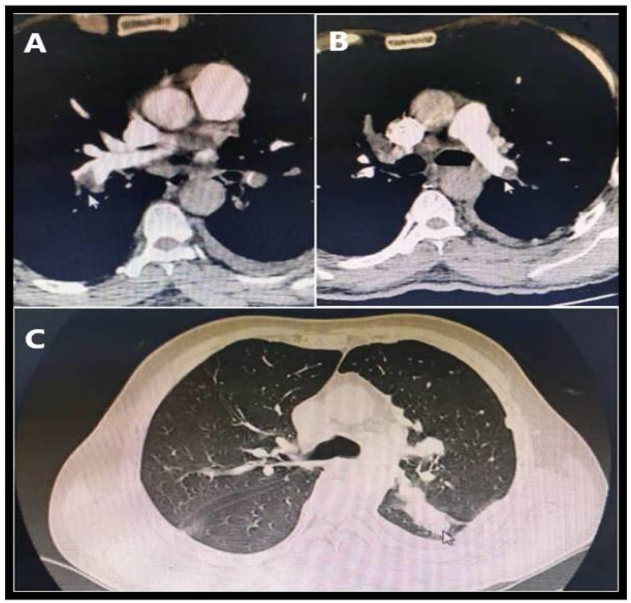

A 47 year male, chronic smoker presented with complaints of acute onset breathlessness, chest pain, palpitations and giddiness. He is a known diabetic on regular medication. He has no prior history of cardiovascular disease. At the time of presentation, he was conscious oriented but tachypneic. His heart rate was 140bpm, blood pressure 80/50mmHg, room air saturation 88% and respiratory rate 36/min. Electrocardiogram showed sinus tachycardia, no ST-T changes. Bedside echocardiography showed RA RV dilation, RV dysfunction, moderate TR and adequate LV function. PE was suspected and features of CTPA done were consistent with pulmonary embolism involving bilateral branch pulmonary arteries, extending into lobar and segmental branches (Figure 3A, B). A well-defined mass was noted in left lower lobe with adjacent pleural based nodules (Figure 3C). Bilateral diffuse parenchymal tumor nodules, bilateral minimal pleural effusion, and mediastinal lymphadenopathy were seen. Reperfusion therapy for acute PE with intravenous streptokinase (250 000 IU as a loading dose over 30 min, followed by 100 000 IU/h over 24 h) was administered after ruling out contraindications to thrombolysis in addition to the initial respiratory and hemodynamic support. He achieved symptomatic relief gradually. He was continued on therapeutic anticoagulation. Pleural fluid cytology and cell block was suggestive of adenocarcinoma, primary lung, negative for driver mutations EGFR, ALK and ROS1. PET CT and CE-MRI brain did not show any additional metastatic foci. A diagnosis of stage IVA adenocarcinoma lung was made. He was started on chemotherapy and continued on oral anticoagulants. He is on regular follow up and is symptomatically better.

Figure 3. A,B. CTPA showing filling defects in distal part of bilateral main pulmonary arteries (arrow).                                                                                                                                                           C. Left lower lobe mass is seen with adjacent pleural nodules.